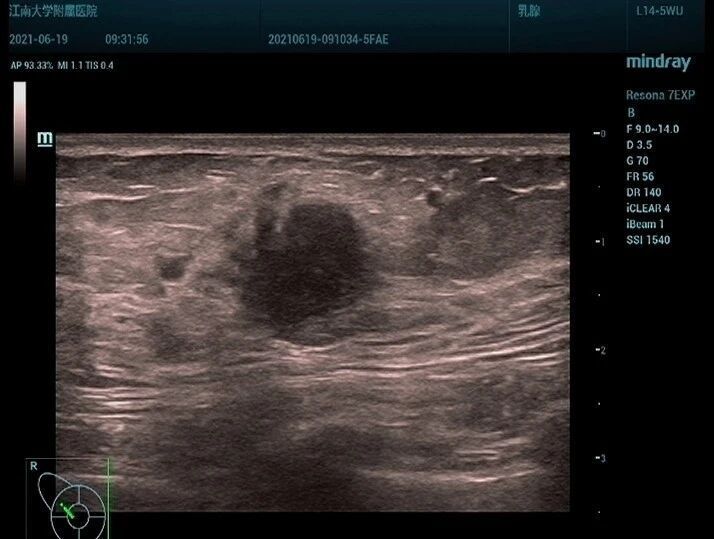

超声于右侧附件区见一囊实性团块,大小约 138 × 98 × 77 mm ,边界清,形态规则,内部回声不均,以实性为主(图 5), CDFI 于实性部分见少许血流信号(图 6), PW 测及低阻动脉血流频谱, RI:0.30 (图 7)。

图 5 右侧附件区见一囊实性团块,大小约 138 × 98 × 77 mm ,边界清,形态规则,内部回声不均